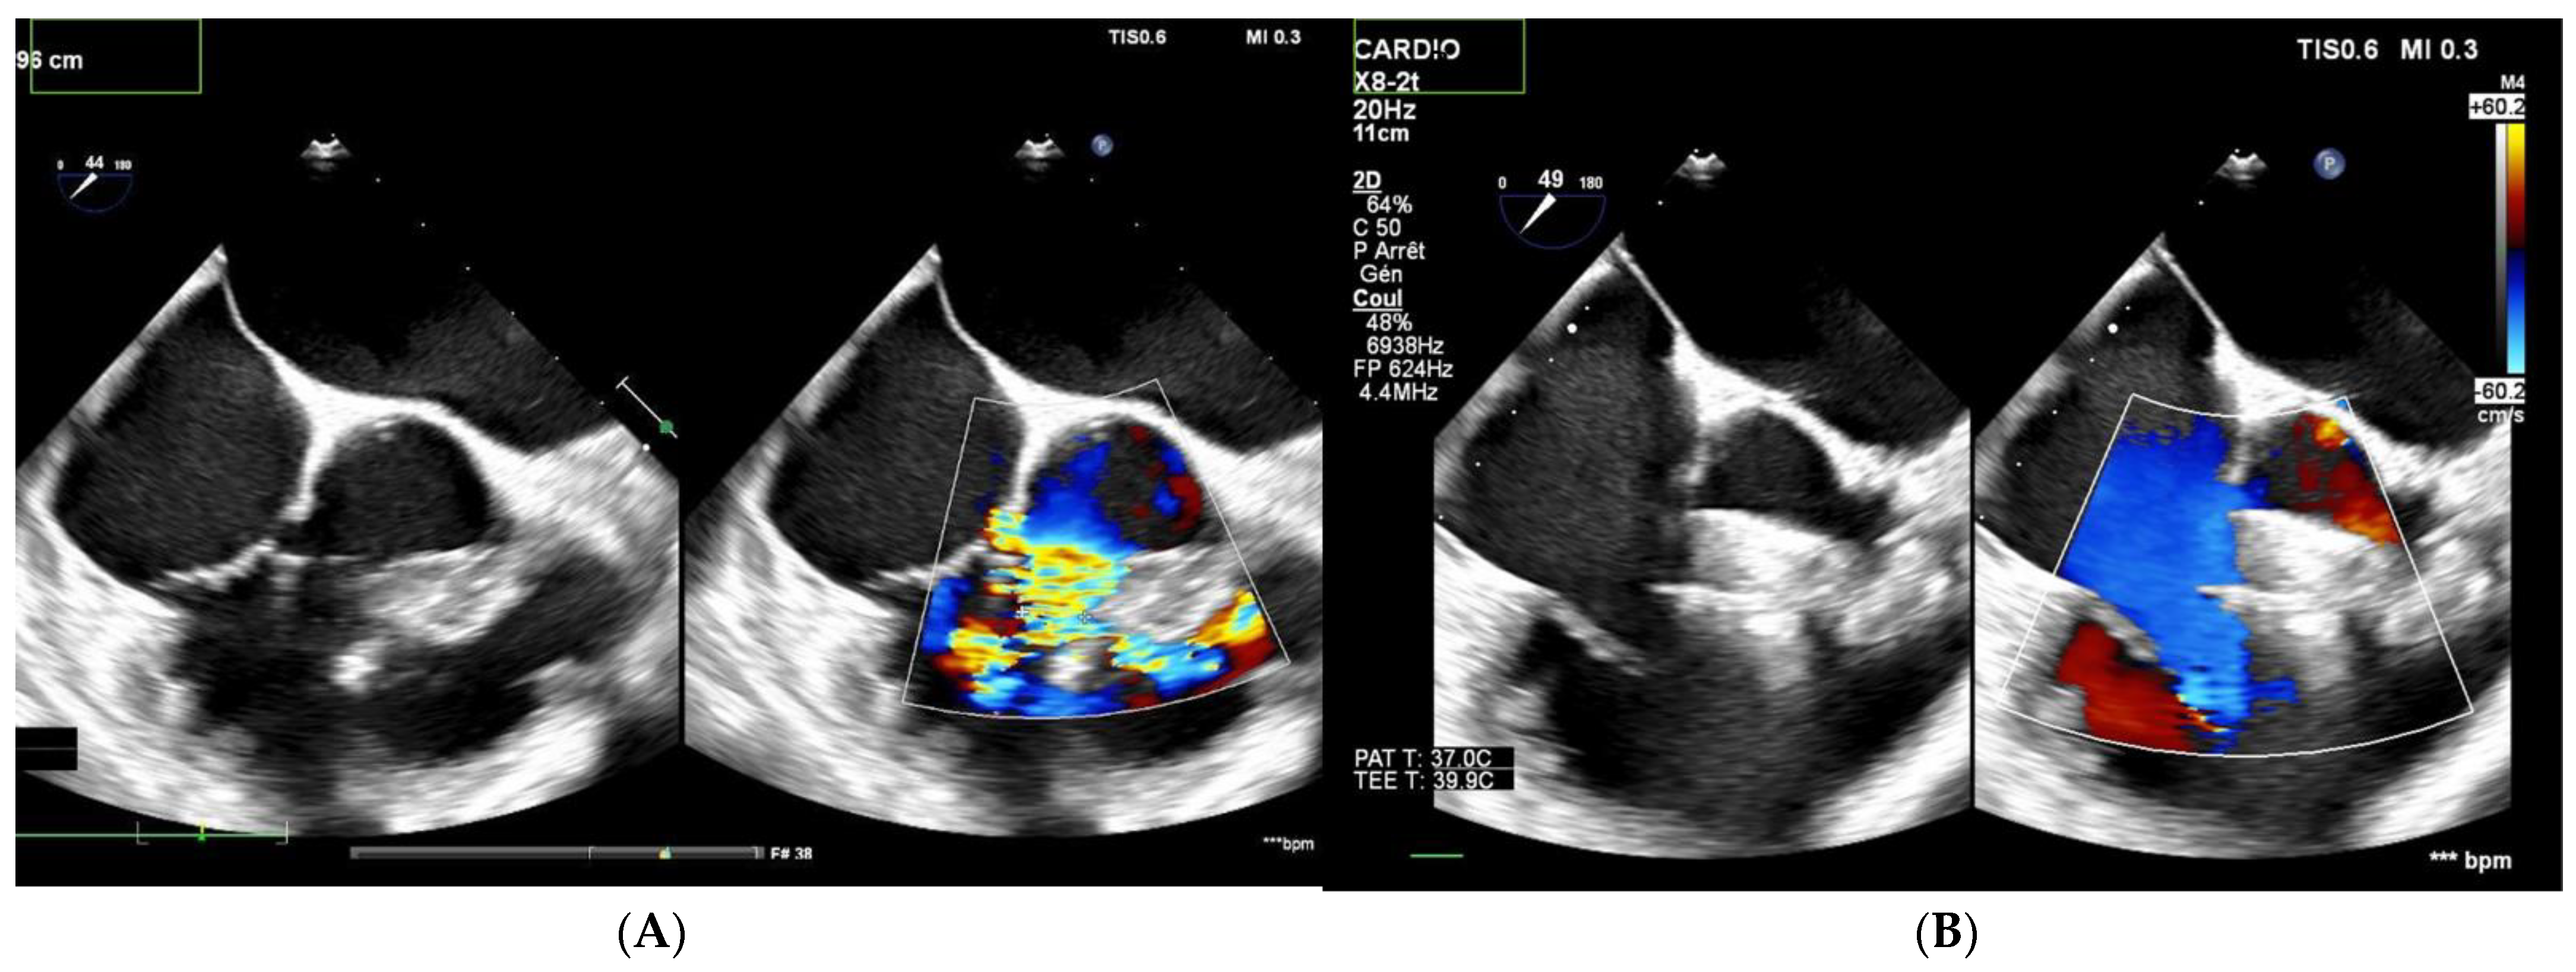

Among the 13 patients with multiple right-sided exits, 7 had no shunt during follow-up (Figure 2 and Figure 3). Among the five patients with both multifenestrated defects and Gerbode-type VSD, three achieved complete occlusion and the other two had tiny residual shunts. All the residual shunts were trivial shunts persistent at 1 and 6 months of follow-up.

Figure 2. Patient with multifenestrated PmVSD. (A) Left: transesophageal echocardiography, notice the 2 jets to the RV. (B) After closure with MFO 14/12 mm device, no shunt is observed on color Doppler echocardiography.